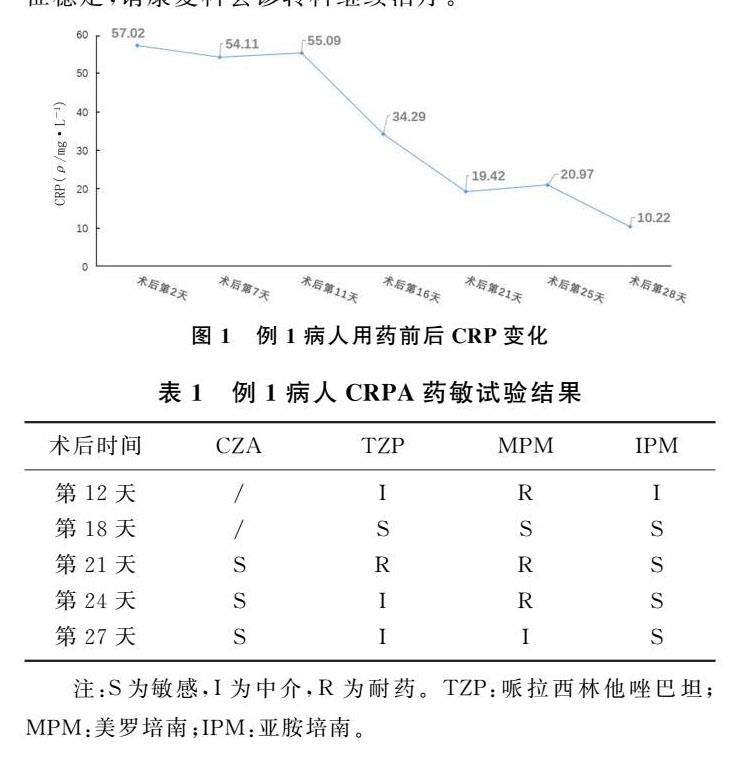

经验介绍 | 临床药师参与碳青霉烯类耐药铜绿假单胞菌抗感染治疗的意义

经验介绍 | 临床药师参与碳青霉烯类耐药铜绿假单胞菌抗感染治疗的意义